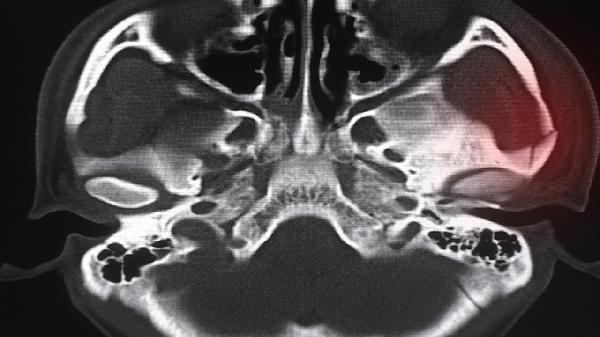

术后早期普遍会出现面部肿胀和皮下淤血,通常1-2周逐渐消退。术中可能触及下颌缘神经分支,导致下唇暂时性麻木感,多数在3-6个月内自行恢复。手术创面若护理不当可能引发感染,需严格遵医嘱使用抗生素预防。截骨线对位不佳可能影响咬合功能,需通过术中三维导航技术规避。过量截骨可能导致轮廓不自然,需术前精确测量骨骼厚度。

建议选择具备四级整形资质的医疗机构进行手术,术前需完成三维CT扫描和咬合模型分析。术后应佩戴弹力头套4-6周帮助塑形,避免早期咀嚼硬物。出现持续发热、剧烈疼痛或异常分泌物需立即复诊。保持口腔清洁,使用医用漱口水预防感染,术后3个月内避免剧烈运动。